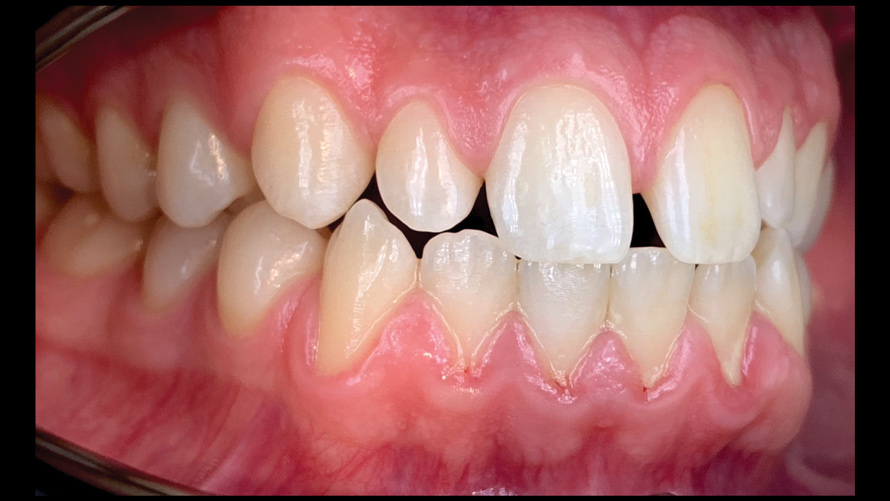

(18.) Tooth shade analysis of value, chroma, and hue taken with a smartphone and an EALS device.

Figure 18

(19.) Tooth shade analysis of value, chroma, and hue taken with a smartphone and an EALS device.

Figure 19